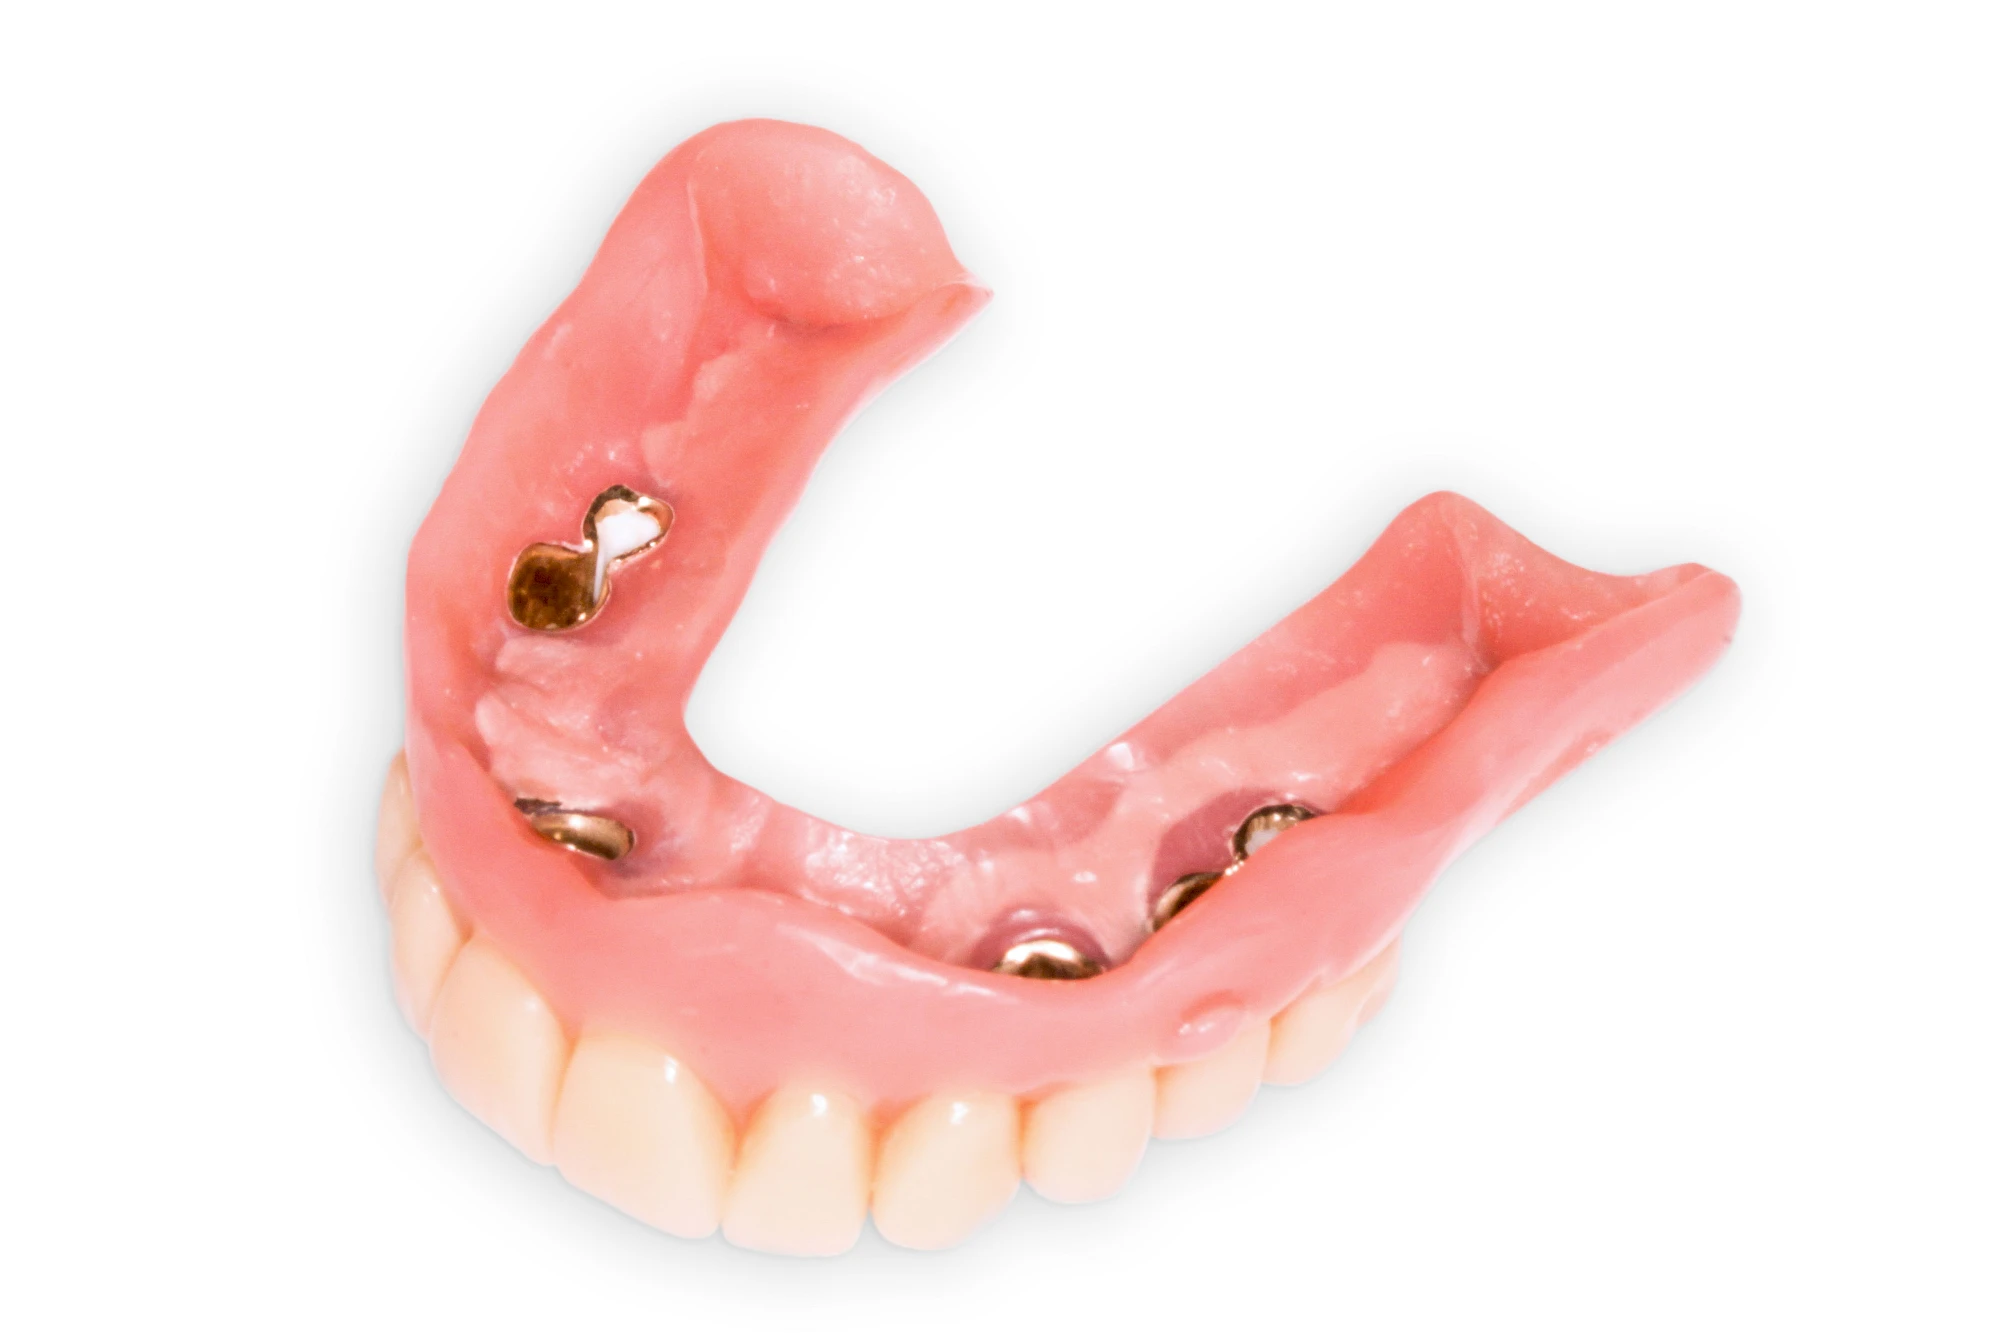

Bei herausnehmbaren Prothesen werden Implantate eingesetzt, um den Halt und den Tragekomfort der Prothesen zu verbessern. Dazu kommen verschiedene Verbindungselemente zum Einsatz:

- Teleskope

- Kugelköpfe

- Tellerförmige Lokatoren

- Stege

- Magnete (selten)